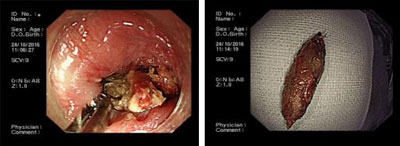

10月24日上午,一名98岁患者因勿吞枣核来我院消化内科就诊,患者于10月22日在当地做过CT检查,报告显示食管上段平声门下水平可见一横行管状高密度,边缘可见结节状略高密度,周围软组织肿胀,家属告知此患者心功能不全病伴心衰、房颤病史,在当地医院就诊因患者异物位置高,内镜下取出难度大,且患者高龄伴有严重原发病,推荐患者到我院就诊。10月24日上午患者转诊至我院,消化内科主任刘吉勇亲自为患者做内镜下异物取出术,在杨崇美主任医师、刘华琳护士长及医护团队配合下,给患者吸氧、心电监护前提下,经过约15分钟时间成功将患者食管上口的枣核取出。